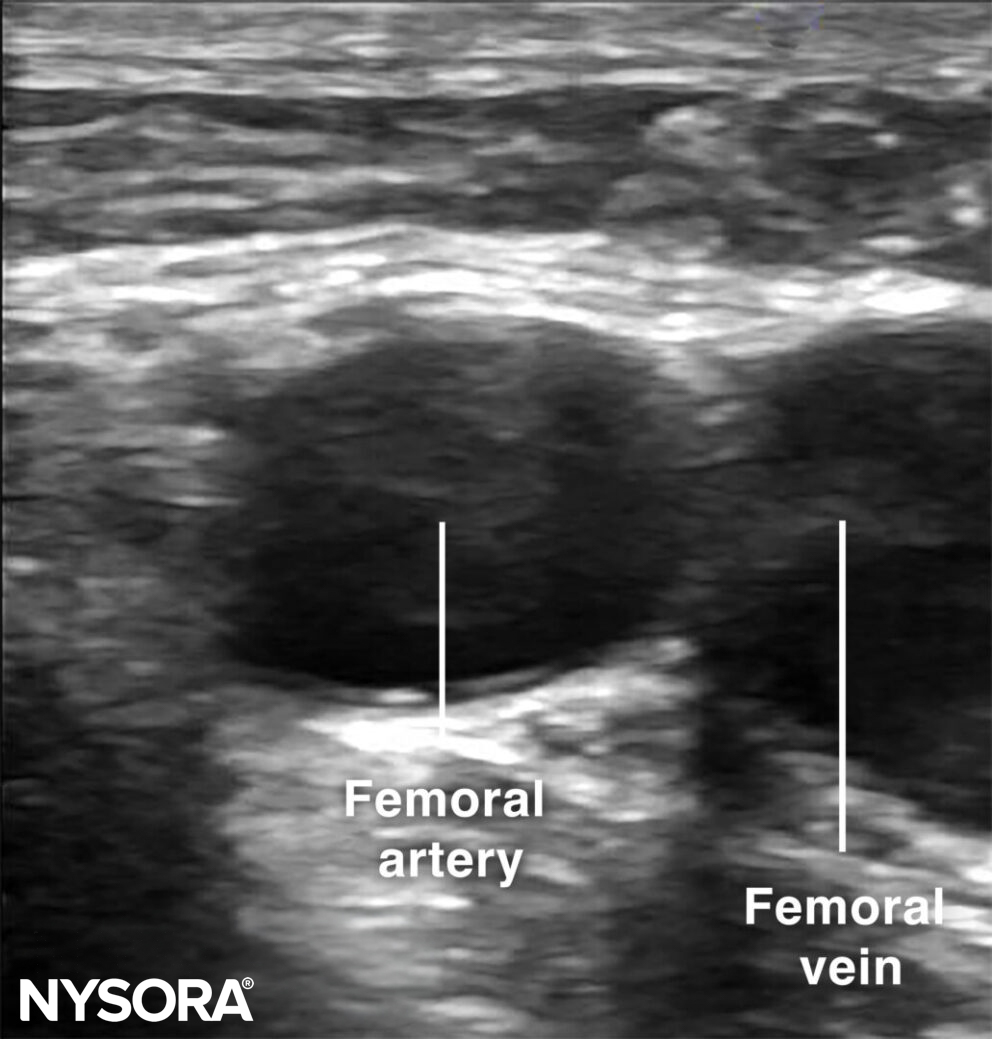

Sonoanatomy for femoral artery cannulation.